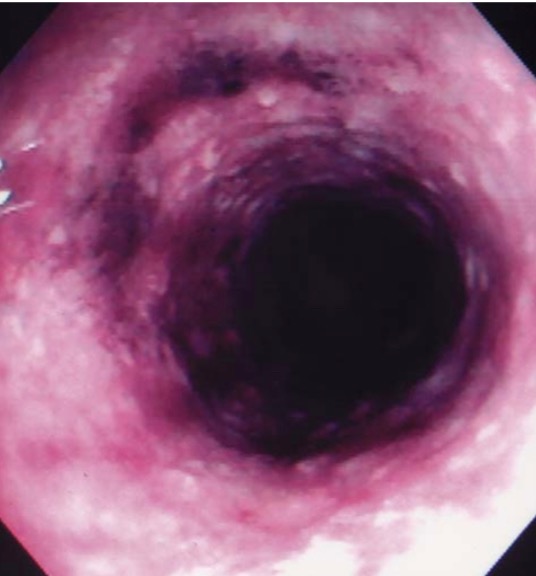

Эндоскопический вид слизистой оболочки сигмовидной кишки через 1 день после введения спиртовой клизмы, показывает слизистую оболочку от пурпурного до чёрного цвета и потерю сосудистого рисунка.